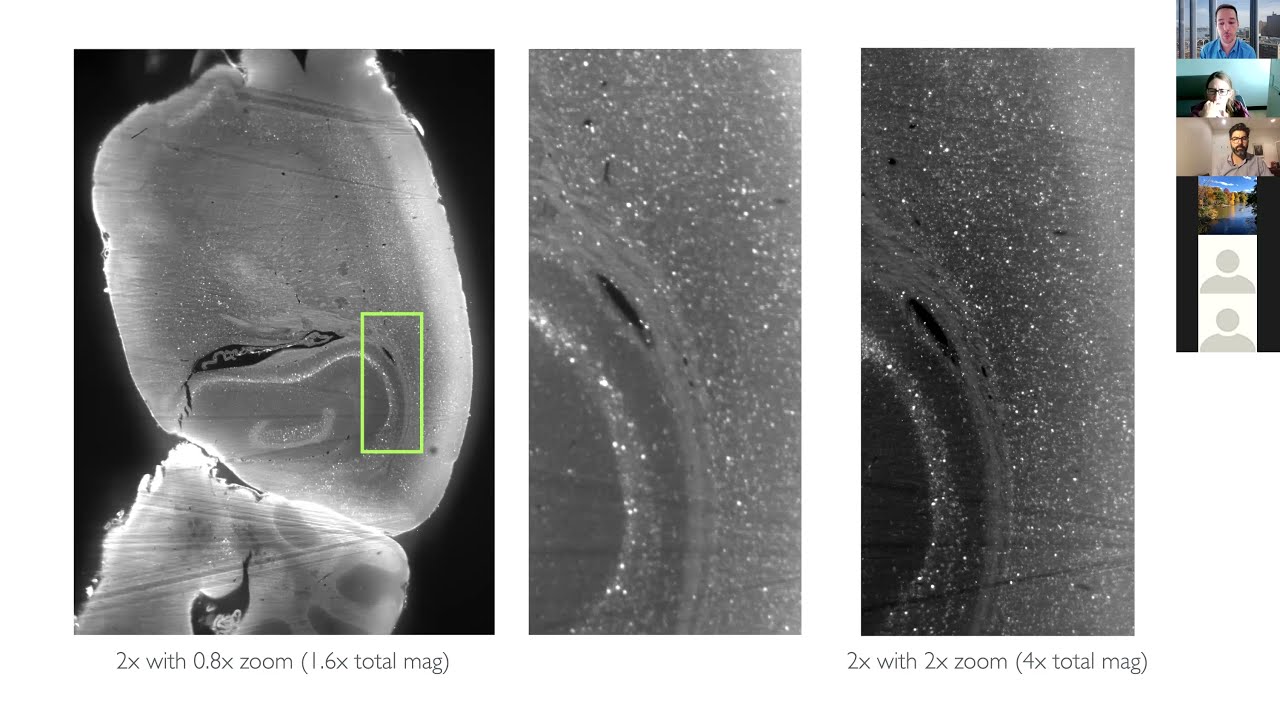

A Practical Guide to Mapping Brain Activity with ClearMap2

Описание: Tutorial for editing and using ClearMap2's CellMap script for activity mapping of cFos positive cells imaged using light sheet microscopy.

Considerations and parameters for imaging cFos and activity markers on the light sheet microscope at the Zuckerman Institute